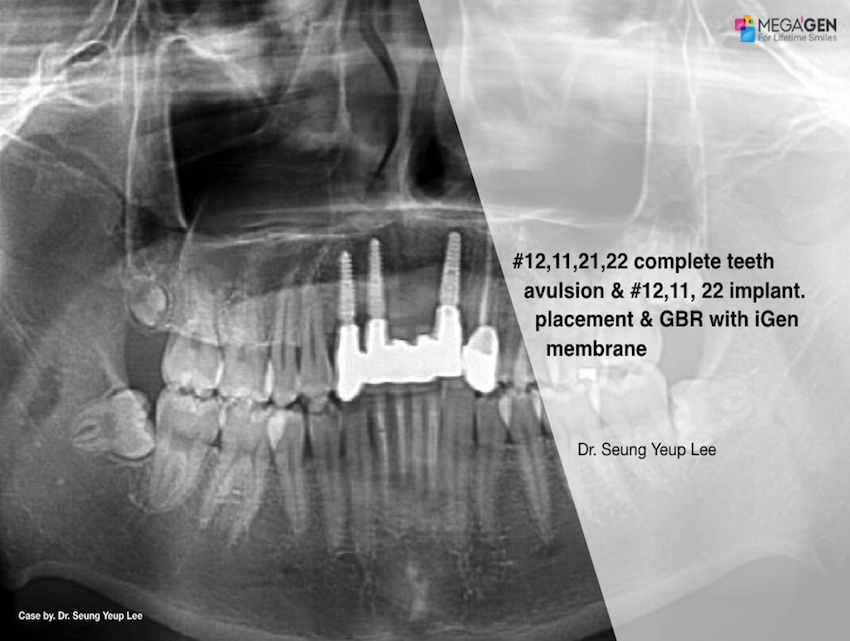

#12,11,21,22 complete teeth avulsion & #12,11,22 implant placement & GBR with i-Gen membrane

Dr. Seung Yeup Lee,Bone regeneration,Aesthetic zone,Maxillary Anterior,#11,#12,#21,#22,GBR,i-Gen,Clinical case

English

2019-10-01

PDF

712.60 Kb

Clinical cases

423